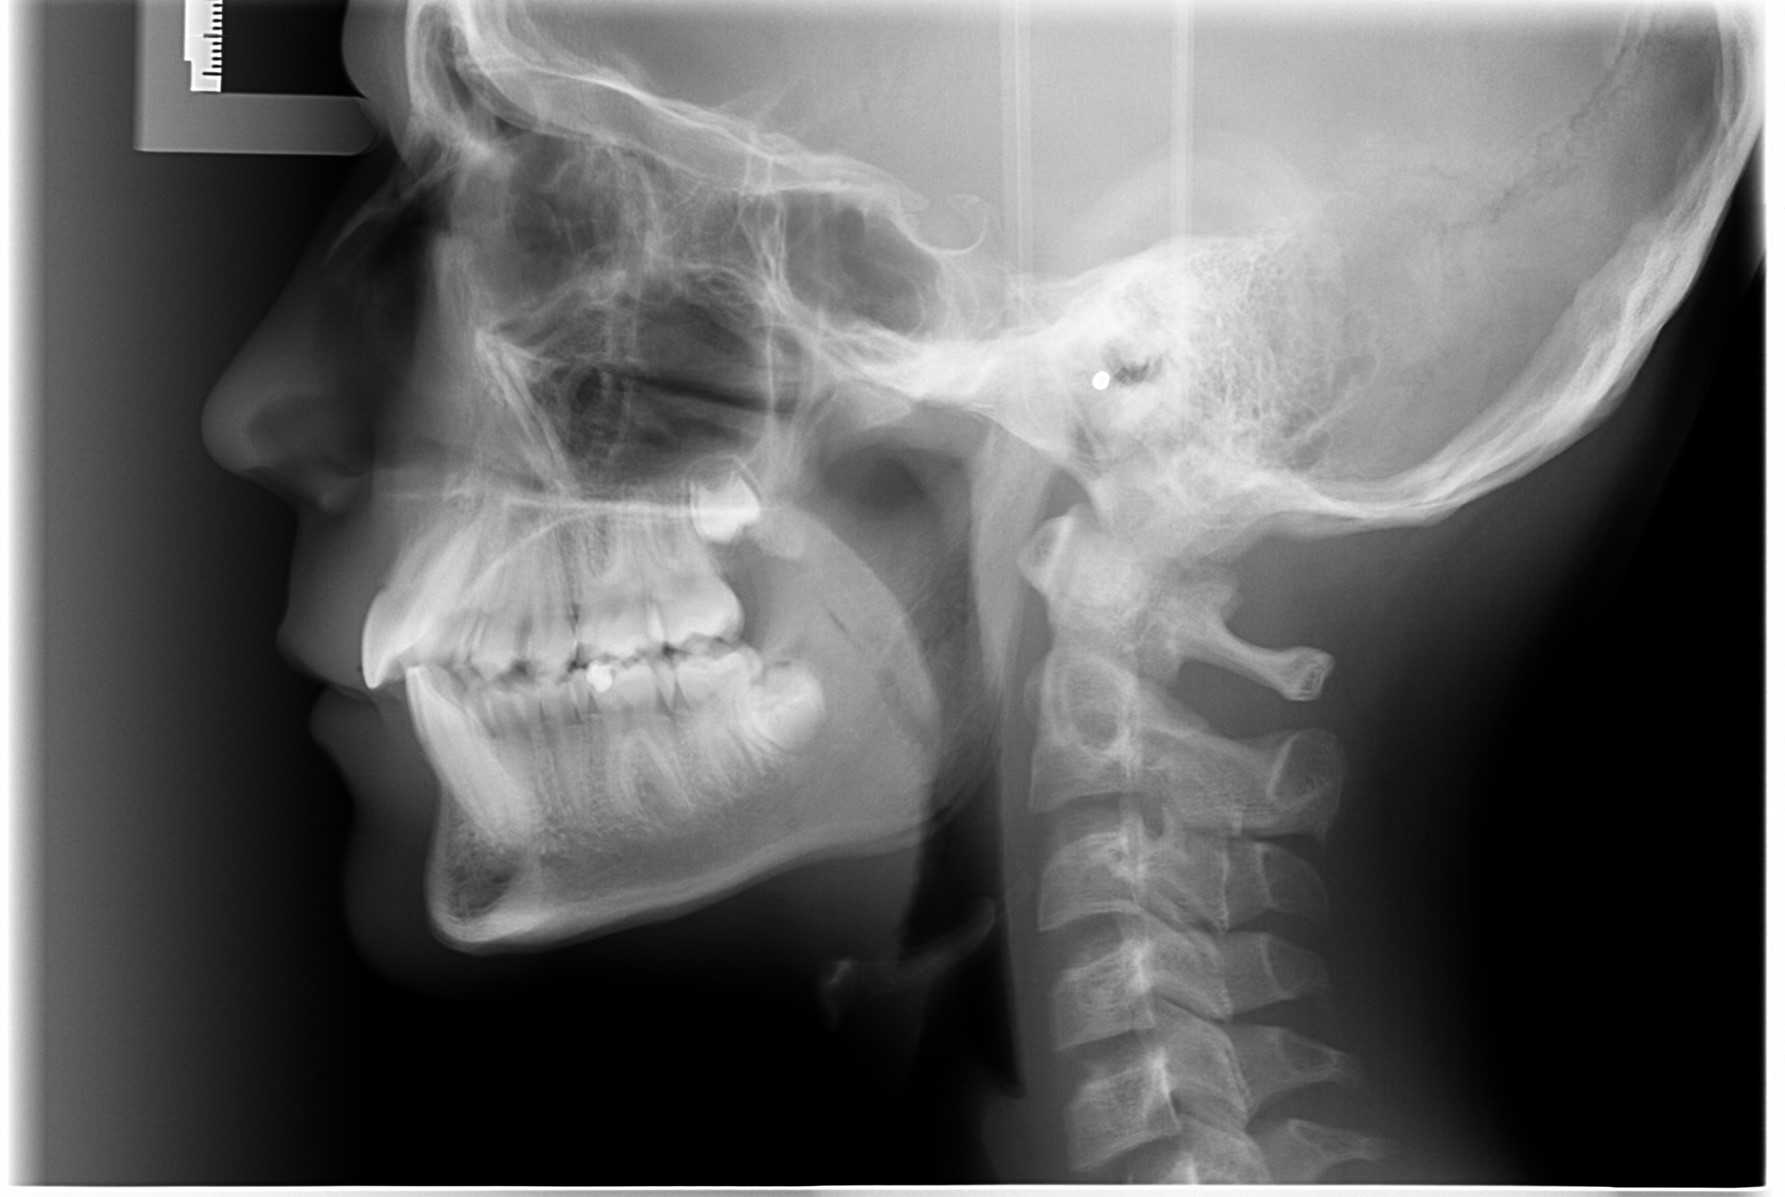

- Vi tager røntgenbilleder af tænder, kæber og hoved.

Når du har takket ja til tandreguleringsbehandling, har du og dine forældre også givet accept til, at vi tager et røntgenbillede ca. hver 6. måned.

Vi tager røntgenbilleder for at kontrollere, om rødderne kan klare belastningen med faste bøjler.